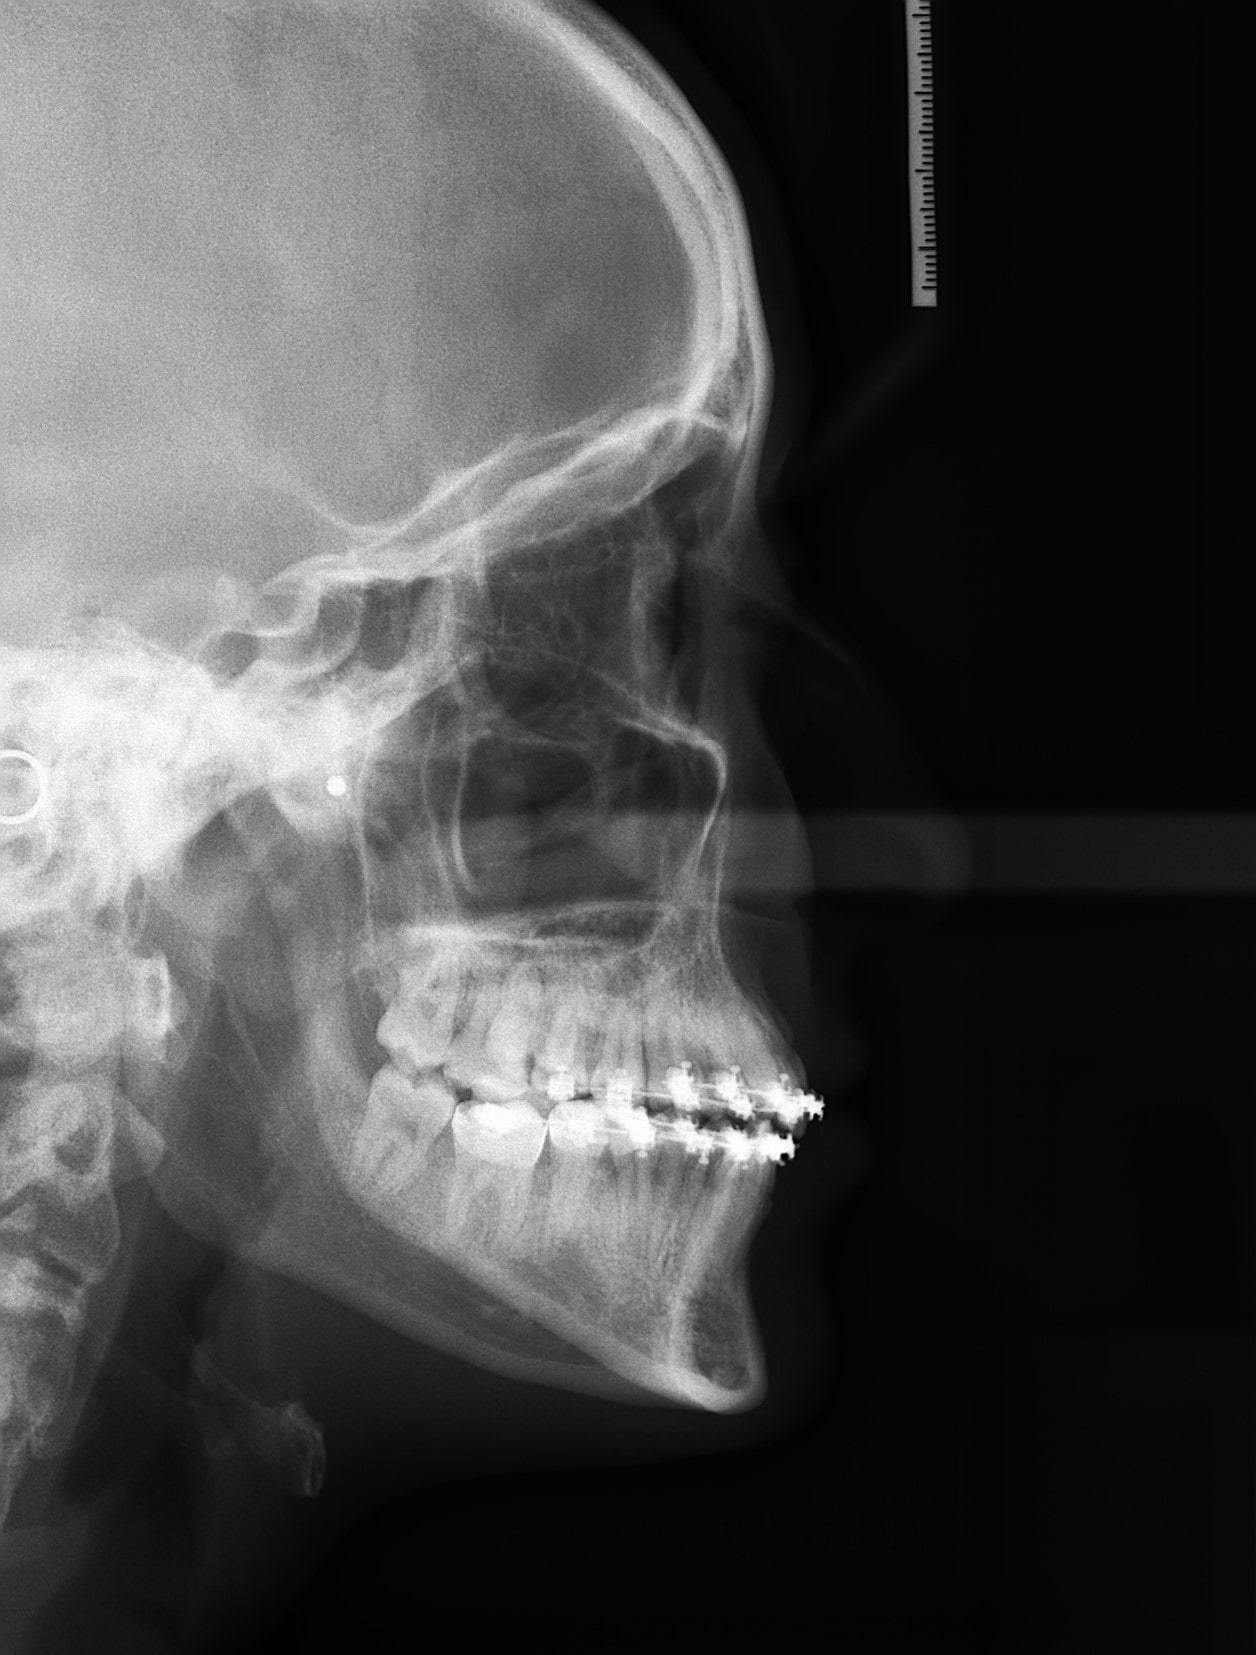

Las intraorales son las radiografías de un conjunto de dientes o un diente en concreto, mientras que las extraorales son la Ortopantomografía muy utilizada para diferentes diagnósticos y la Teleradiografía Lateral de Cráneo para estudios de ortodoncia.